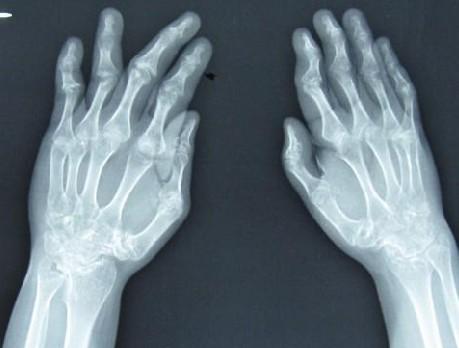

风湿病这种病情给人最大的痛苦就是有的时候酸疼酸疼的,让大家都不知道怎么面对,时而好,时而疼的现象,大家不知道怎么治疗,下面我们就看下风湿病的发病原因,希望大家了解自身风湿病的发病原因,做好治疗。

1.反应:机体对外源性或内源性抗原物质直接或通过巨噬细胞呈递的刺激,使相应T-细胞活化,部分T-细胞产生大量多种致炎性细胞因子造成各类组织器官不同程度的损伤或破坏;部分T-细胞再激活B-细胞,产生大量抗体,直接或与抗原结合形成复合物,使组织或器官受到损伤或破坏。此外由单核细胞产生的单核细胞趋化蛋白如MCP-1等,也可参与炎症反应。大部分风湿性疾病,或由于感染产生的外源性抗原物质,或由于体内产生的内源性抗原物质,可以启动或加剧这种自身反应,血清内可出现多种抗体。

2. 遗传背景:近年来的研究证明一些风湿性疾病,特别是结缔组织病,遗传及患者的易感性和疾病的表达密切相关,对疾病的早期或不典型病例及预后都有一定的意义;其中HLA人类组织白细胞抗原最为重要。

3. 感染因素:根据多年来的研究阐明,多种感染因子,微生物产生的抗原或超抗原,可以直接或间接激发或启动反应。

4. 内分泌因子:研究证明,雌激素和孕激素的失调、与多种风湿病的发生有关。

5. 环境与物理因素:如紫外线可以诱发SLE 。>>>风湿病较好的治疗方法是什么?点击免费咨询专家